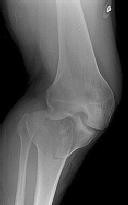

**CLINICAL SITUATION**

Figures 1 and 2 are the radiographs of a 35-year-old man who is brought into the emergency department after a motor vehicle collision. He is complaining of isolated knee pain. Examination reveals swelling, blood filled blisters, popliteal ecchymosis, joint line pain, and limited knee joint motion. His pulses and sensation are normal.

This knee injury is best described as a